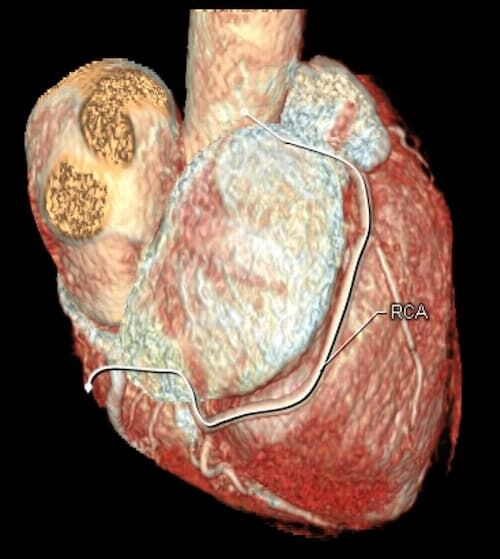

Herz

Durchführung am Standort im Diakonissenkrankenhaus